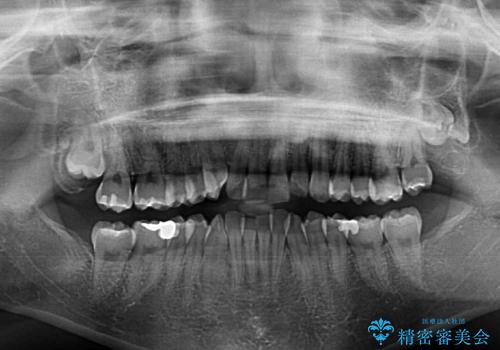

- 上下前歯のデコボコを気にして来院された患者様です。

デコボコが強いため、非抜歯で矯正をすると出っ歯仕上がりとなるため、上下左右の第一小臼歯4本を抜歯することとしました。